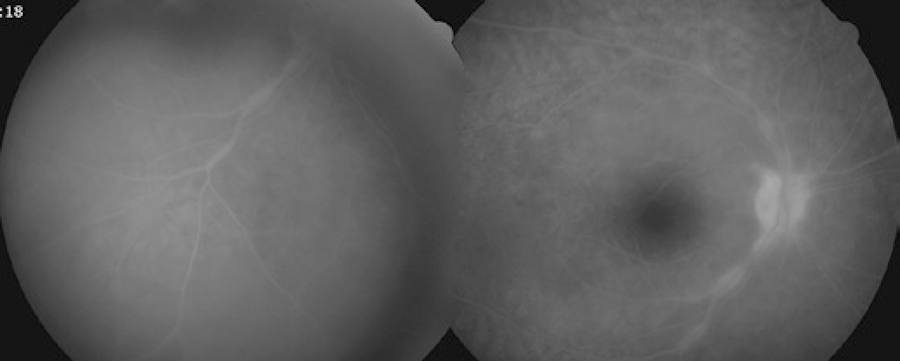

A 44-year-old male patient presented to our clinic with symptoms of floaters in both eyes for a week. The best corrected visual acuity (BCVA) was 0.8 on the right eye and 0.9 on the left, and intraocular pressures were normal. The case had been followed up for mucosal LP for the last 10 years at another center. Anterior segment examination was normal for both eyes. Bilateral intensive vitritis and peripheral vascular sheathing were observed on fundus examination (Figure 1). FA investigation revealed staining and leakage of the mid-peripheral vessels in the early stage and of the optic disc and surrounding vessels in the late stage (Figure 2). The patient had no history of urogenital or oral ulceration, skin rash, weight loss, cough, night sweats, lymphadenopathy, arthritis, arthralgia, neurological symptoms, gastrointestinal symptoms, travel to foreign territories, or contact with animals. No evidence of pathology was found in tests performed to investigate the etiology of retinal vasculitis, and complete blood count, biochemical tests (glucose, urea, creatinine, electrolytes, and liver and kidney function tests), erythrocyte sedimentation, C-reactive protein, FTA-ABS, VDRL, Lyme IgM and IgG, HIV serology, urine analysis, rheumatoid factor (RF), anti-neutrophil antibody (ANA), tuberculin skin test (PPD), and chest X-ray tests were all normal. The results of cranial and orbital magnetic resonance imaging were normal. Consultations with various departments were performed to exclude Behcet's disease, sarcoidosis, systemic lupus erythematosus, multiple sclerosis, and tuberculosis, some of the most common etiologic causes of retinal vasculitis. Because of suspected LP, fluocortolone tab (1 mg/kg), cyclosporine tab (2 x 100 mg), and azathioprine tab (2 x 50 mg) were started as systemic treatment. No topical treatment was used. Corticosteroid treatment was gradually decreased and eventually stopped. BCVA fully recovered bilaterally at the first month of follow-up, and the vitritis and peripheral vascular sheathing had regressed. BCVA and anterior and posterior segment examinations were normal within the first year follow-up; therefore, the immunosuppressive treatment was discontinued (Figure 3).

Figure 2 FA shows staining and leakage of the mid-peripheral vessels in the early stage and of the optic disc and surrounding vessels in the late stage.